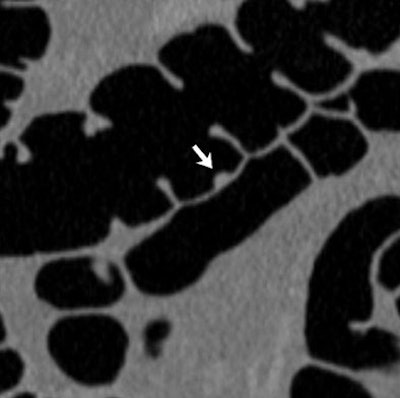

"Multiple polypoid lesions measuring up to 9 mm and located within matching colonic segments were confirmed at optical colonoscopy performed several hours after CT colonography," Andrews et al wrote. "The lesions, however, were not mucosal polyps, but instead were well-defined raised submucosal vascular blebs with a distinctive bluish hue. Biopsy was not performed because of the vascular nature of the lesions, combined with the fact that the endoscopic appearance was characteristic and diagnostic."

| A 64-year-old man was referred for initial colorectal screening. Endoluminal 3D (above and below) and coronal 2D (bottom) images from screening CT colonography showed multiple subcentimeter polypoid lesion (arrows). Images below and bottom show the same lesion on 3D and 2D, respectively. Lesions were all of soft-tissue attenuation and measured up to 9 mm. Images reprinted with permission of the American Roentgen Ray Society (ARRS) from Lee et al, AJR 2006; 186:1113-1115. |